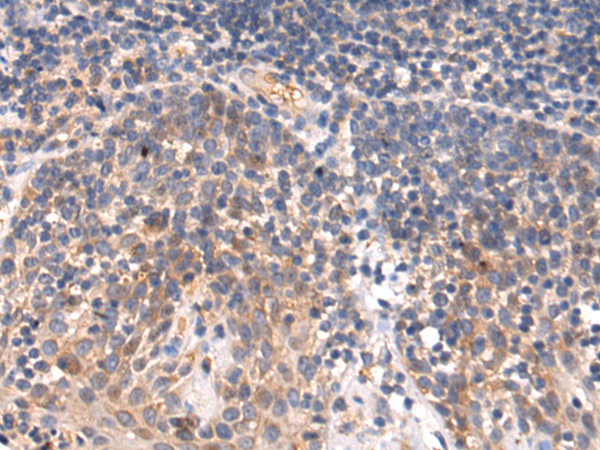

ELISA, WB, IHC |

IHC positive control: |

Human brain |

IHC Recommend dilution: |

20-100 |